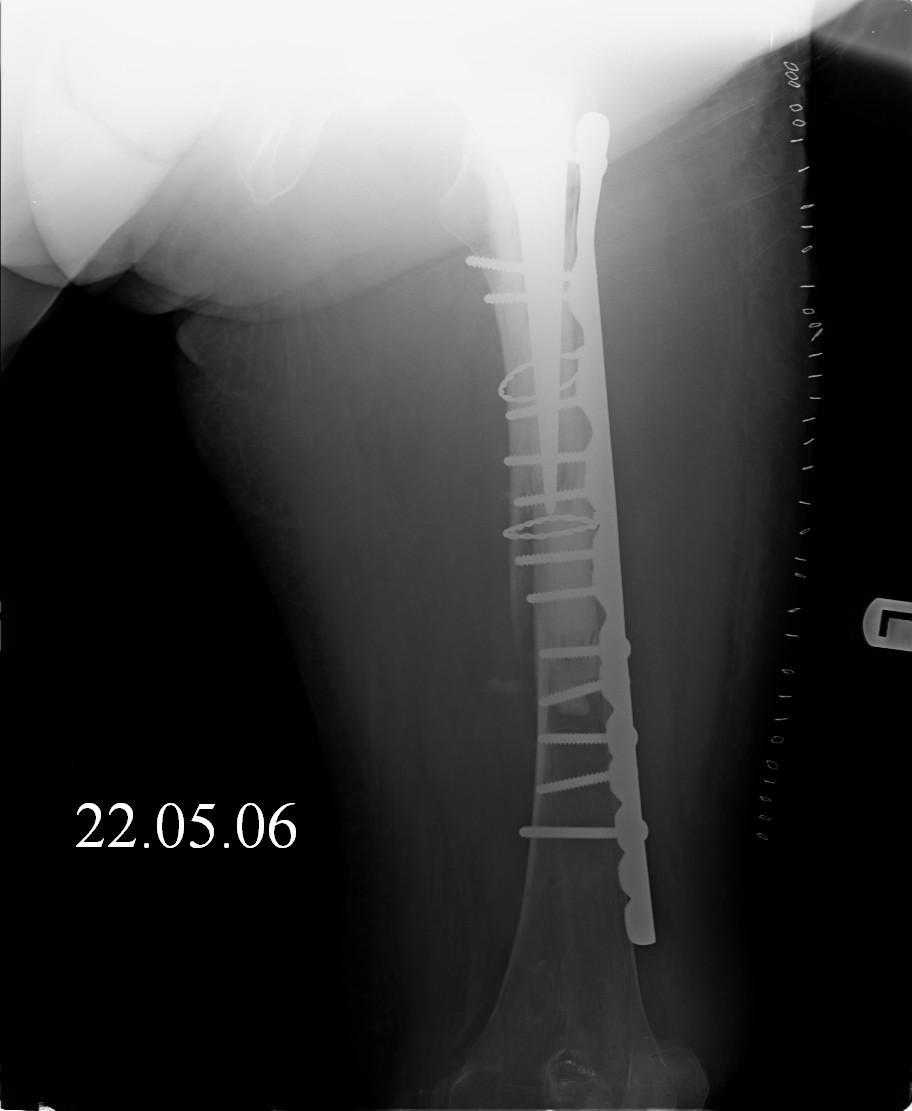

Female, rheumatoid, THA in 2003, car accident in 2006, failed plating. Nailing in Oct 2007. The nail is solid with hollow proximal part where the stem is docked. Last images are in 1 year after

nailing.

Спасибо за обсуждение. После нескольких дней тракции аппаратом сделали. Попытка закрытой репозиции не удалась из-за смещения по ширине, мешали фрагменты цемента. После их удаления репозиция получилась. Еще убрали немного цемента с ножки по латерльной стороне, чтобы обнажить 40-50 мм ее дистальной части, для плотной посадки гвоздя. Дальнейшее введение гвоздя было несложным. Протез показался нам стабильным в проксимальной части как латерально, так и медиально. Картинки в приложении.

THX for the discussion. After few days of traction by ex-fix the surgery was performed. An attempt of closed nailing was unsuccesful because of fragment translation, which was blocked by cement fragments. After removal of broken cement pieces reduction was reached "automagically". Also some cement from lateral part was removed by

chisel to expose distal 40-50 mm of the stem to allow tight fit of the nail. Further fixation by the nail was pretty easy and straightforward. Images attached. The stem looked stable in its proximal part both laterally and medially. Comments/critics are welcome.